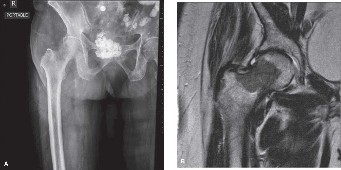

A 47 year old female with metastatic thyroid cancer has progressive left hip pain. X-rays are shown in Figure…